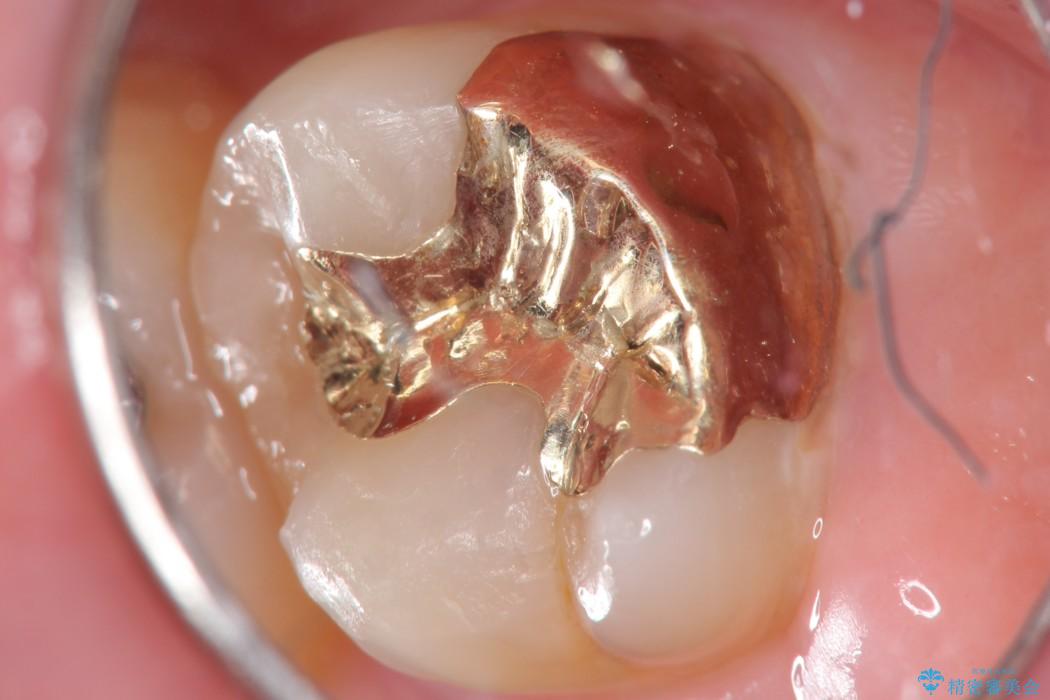

上顎左の一番奥の歯が深い虫歯になって脆くなり、更にその状態に強く噛みしめたわけではない通常の咬合力が加わったことで歯が欠けてしまっていました。

今回は一番奥の歯という位置と、噛み合わせ、清掃状態を加味して適合の高く長持ちするゴールドインレーにて治療することとしました。

ゴールドインレー

ゴールドインレーはセラミックより強度高く、使用される金合金や白金加金は汚れの付きにくいという特徴を持っており、耐用年数が長いことが特徴としてあります。特に奥歯など強く力が欠けられる箇所に適しています。